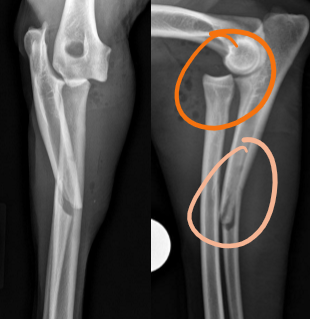

32

New cards

Type 2 physeal fracture

Fracture running through physis and metaphysis

<p>Fracture running through physis and metaphysis</p>

33

Type 3 physeal fracture

Fracture running through the physis and epiphysis

<p>Fracture running through the physis and epiphysis</p>

34

Type 4 physeal fracture

Combo of 2 and 3, runs from metaphysis through the physis and out the epiphysis

<p>Combo of 2 and 3, runs from metaphysis through the physis and out the epiphysis</p>